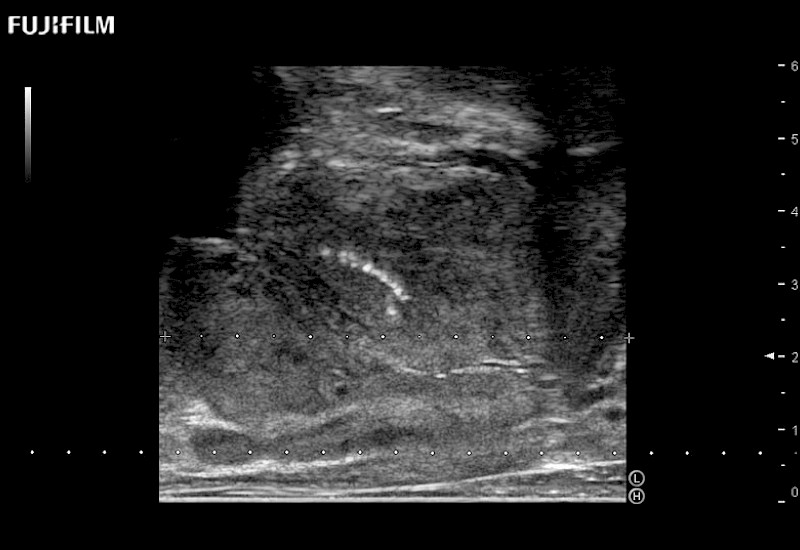

Abdominal transducer for biopsy, bladder and renal applications.

Main Specifications: